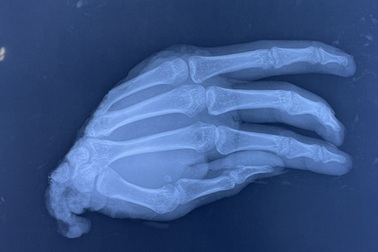

Nối thành công 28 bàn tay đứt lìaKhoa vi phẫu bệnh viện Chấn thương Chỉnh hình (BV CTCH) đã phẫu thuật thành công 28 bàn tay bị đứt lìa, 348 trường hợp đứt gân duỗi, 2 trường hợp ngón tay lột găng...

Nối thành công bàn tay đứt lìa cho bệnh nhi 14 tháng tuổiLần đầu tiên khoa Vi phẫu, bệnh viện Chấn Thương Chỉnh Hình TPHCM, đã phẫu thuật nối thành công 3 ngón tay đứt lìa của một bệnh nhi mới 14 tháng tuổi.

Đồng Nai: 10 tiếng nối bàn tay ướp lạnh 5 tiếngBằng kỹ thuật mổ vi phẫu, ê kíp bác sĩ bệnh viện đa khoa Thống nhất đã nối thành công bàn tay đứt lìa cho thanh niên 20 tuổi.